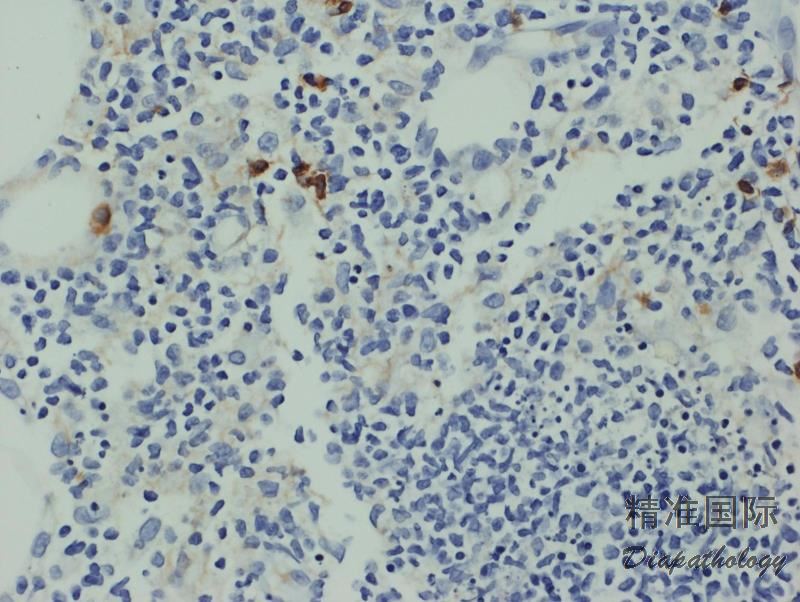

免疫表型:肿瘤细胞 CD3+、CD2+、CD56+、细胞毒分子+、TCR-δ1+、 βF1-、CD4-、CD8-(少数+)、CD5-,有的病例可 TCR-δ1+、 βF1+,EBER-。

免疫组织化学染色:

肿瘤细胞 CD3+、CD2+、CD56+、细胞毒分子+、TCR-δ1+、 βF1-、CD4-、CD8-(少数+)、CD5-。